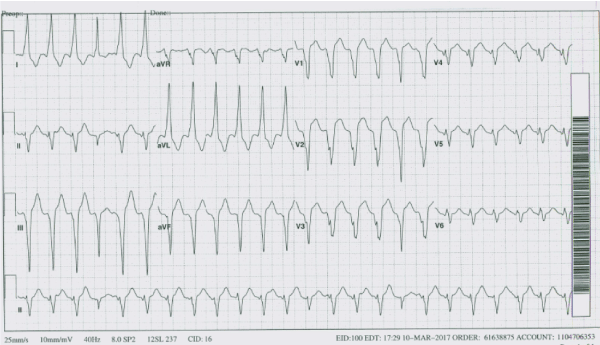

A 71 YO woman with ischemic heart disease, s/p ICD for history of cardiac arrest on Mexiletine presented to ED after receiving multiple ICD shocks. On physical examination, she was tachycardic at 140 beats/min and BP was 139/75 mmHg. Initial EKG showed LBBB morphology. Laboratory data was significant for elevated troponin of 0.68 which was thought to be due to ICD shocks. While she was being evaluated she went into a wide complex tachycardia and was shocked by her ICD again. Patient was loaded with amiodarone and continued on mexiletine. ICD device interrogation revealed single lead ICD was functioning well and multiple episode of VT noted and appropriately detected and treated with ATP and shock therapy. On amiodarone, her arrhythmia burden appeared to have decreased. Patient had diagnostic Left heart catheterization(LHC) done, which demonstrated patent LAD stent and no significant coronary stenosis. Echocardiogram demonstrated LV apical dyskinesia and an aneurysmal deformity with LVEF mildly reduced.

Figure 1: EKG Clinical Ventricular Tachycardia.